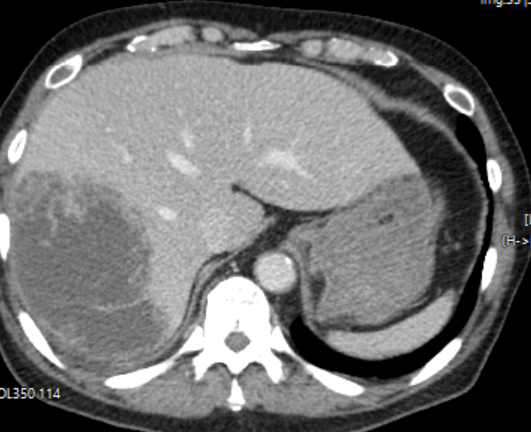

CT 촬영 결과는 충격적이었다.

환자의 우측 간의 절반정도가 농양화 되어 있었던 것이었다.

화농성 간농양의 양상을 보이고 있었고, 다행히 낮시간에 내원한 환자였기에 나는 곧바로 영상의학과 인터벤션 팀에 배농을 위한 경피적 삽관술을 의뢰하면서, 소화기내과로 환자 입원을 의뢰하였다.